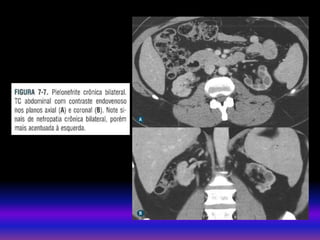

• TAC Sem contraste(litiases). uso contraste Depende da função renal . Util em doenças parenquimatosas ou vasculares. Há risco de NIC Pacientes com DRC estágio 3 – 4 se recomenda: Protocolos com baixa dose de contraste não ionico 60 – 100 ml. Útil hidratação endovenosa antes e após a exposição ao meio de contraste : SSN 250 ml/h x 4 horas (antes e depois) MÉTODOS DE IMAGEM